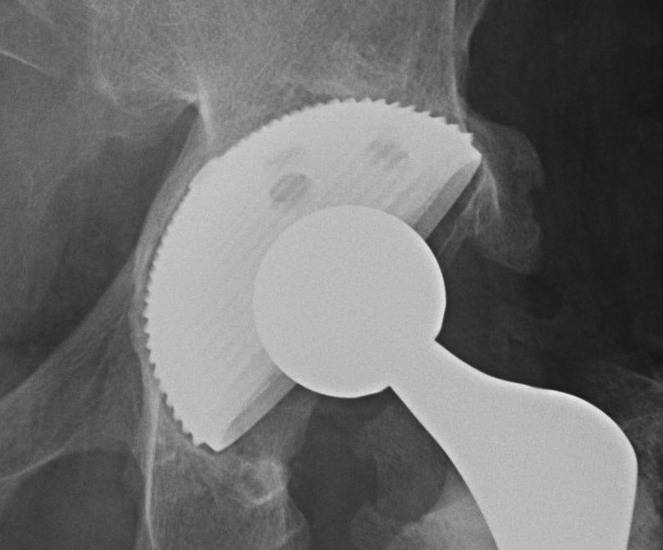

1. Uncemented Jumbo rim fit cup

Indications

- > 50% host bone available for ingrowth

- > 2/3 rim intact

Technique

- implant in usual position

- preferentially ream anteriorly

- preserve posterior column

- some uncovering superiorly allowed

- usually augment with screws

- +/- postoperatively NWB 6/52

Results

- 12-15 year survival between 81-96%